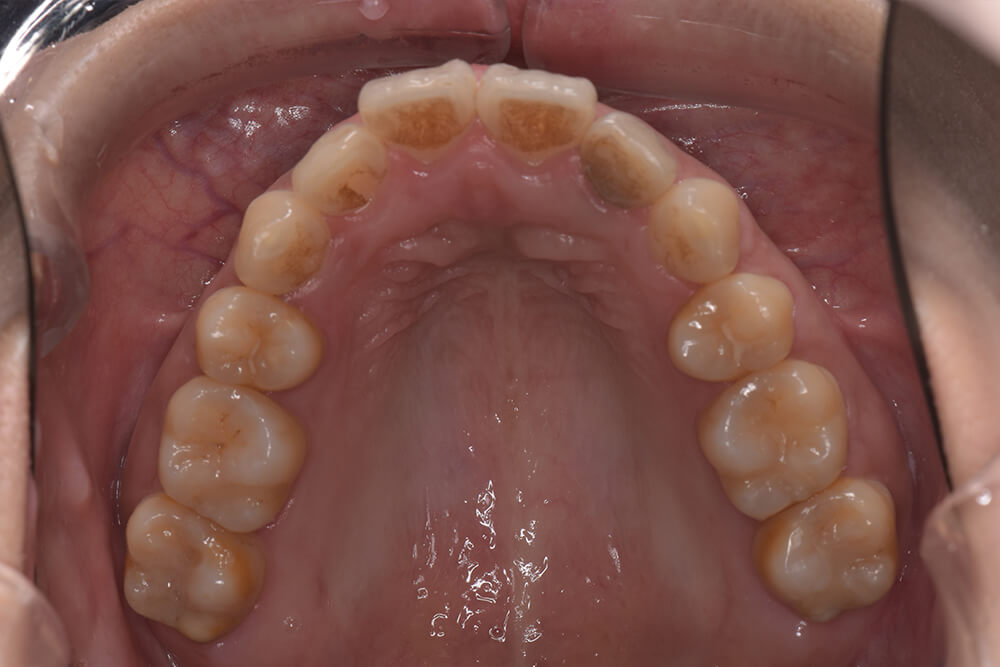

CASE06

Before

After

| コース | 7回コース |

|---|---|

| IPR | 1回 |

| 治療期間 | 10ヶ月 |

| 治療費 | 256,300円 |

| 年齢・性別 | 40代男性 |